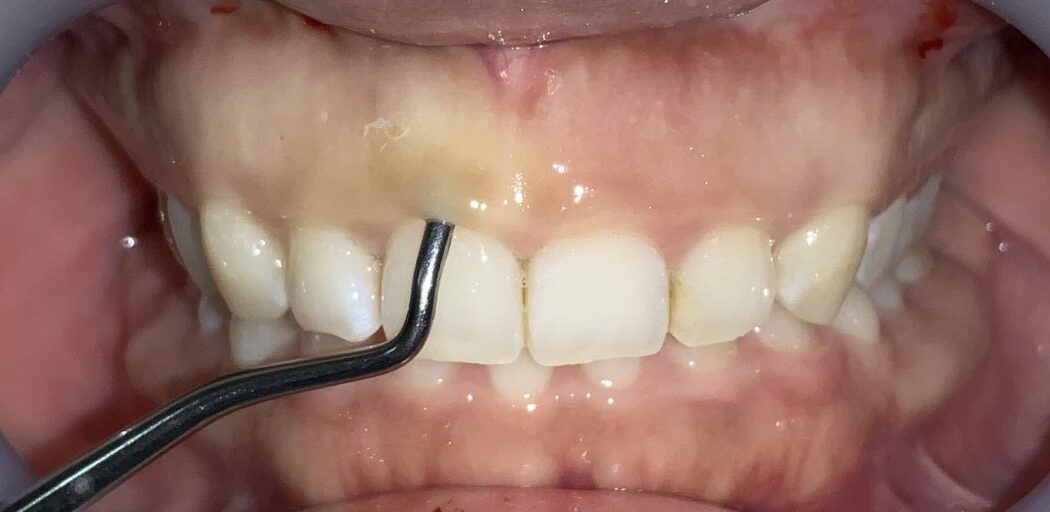

一番気になる、前歯の歯と歯ぐきの位置状態の検査します。

こんなに歯ぐきがかぶさっています。

反対側の歯も調べてみます。前歯の形はとても大切ですから、慎重に検査を進めます。

この歯も同じように、たくさんの歯ぐきが、かぶさっています。